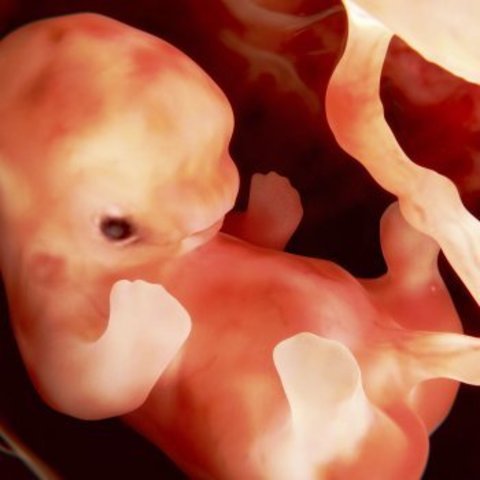

SEMANA 7

Alrededor de esta semana, el embrión se convierte en feto, en esta fase, los tejidos y órganos formados durante el periodo embrionario comienzan a madurar, el esqueleto comienza a tomar forma, al igual que el cordón umbilical comienza a ensancharse.

SEMANA 6

Su cabeza es demasiado grande en comparación de su cuerpo. Las fibras de los músculos así como los pulmones comienzan a desarrollarse.